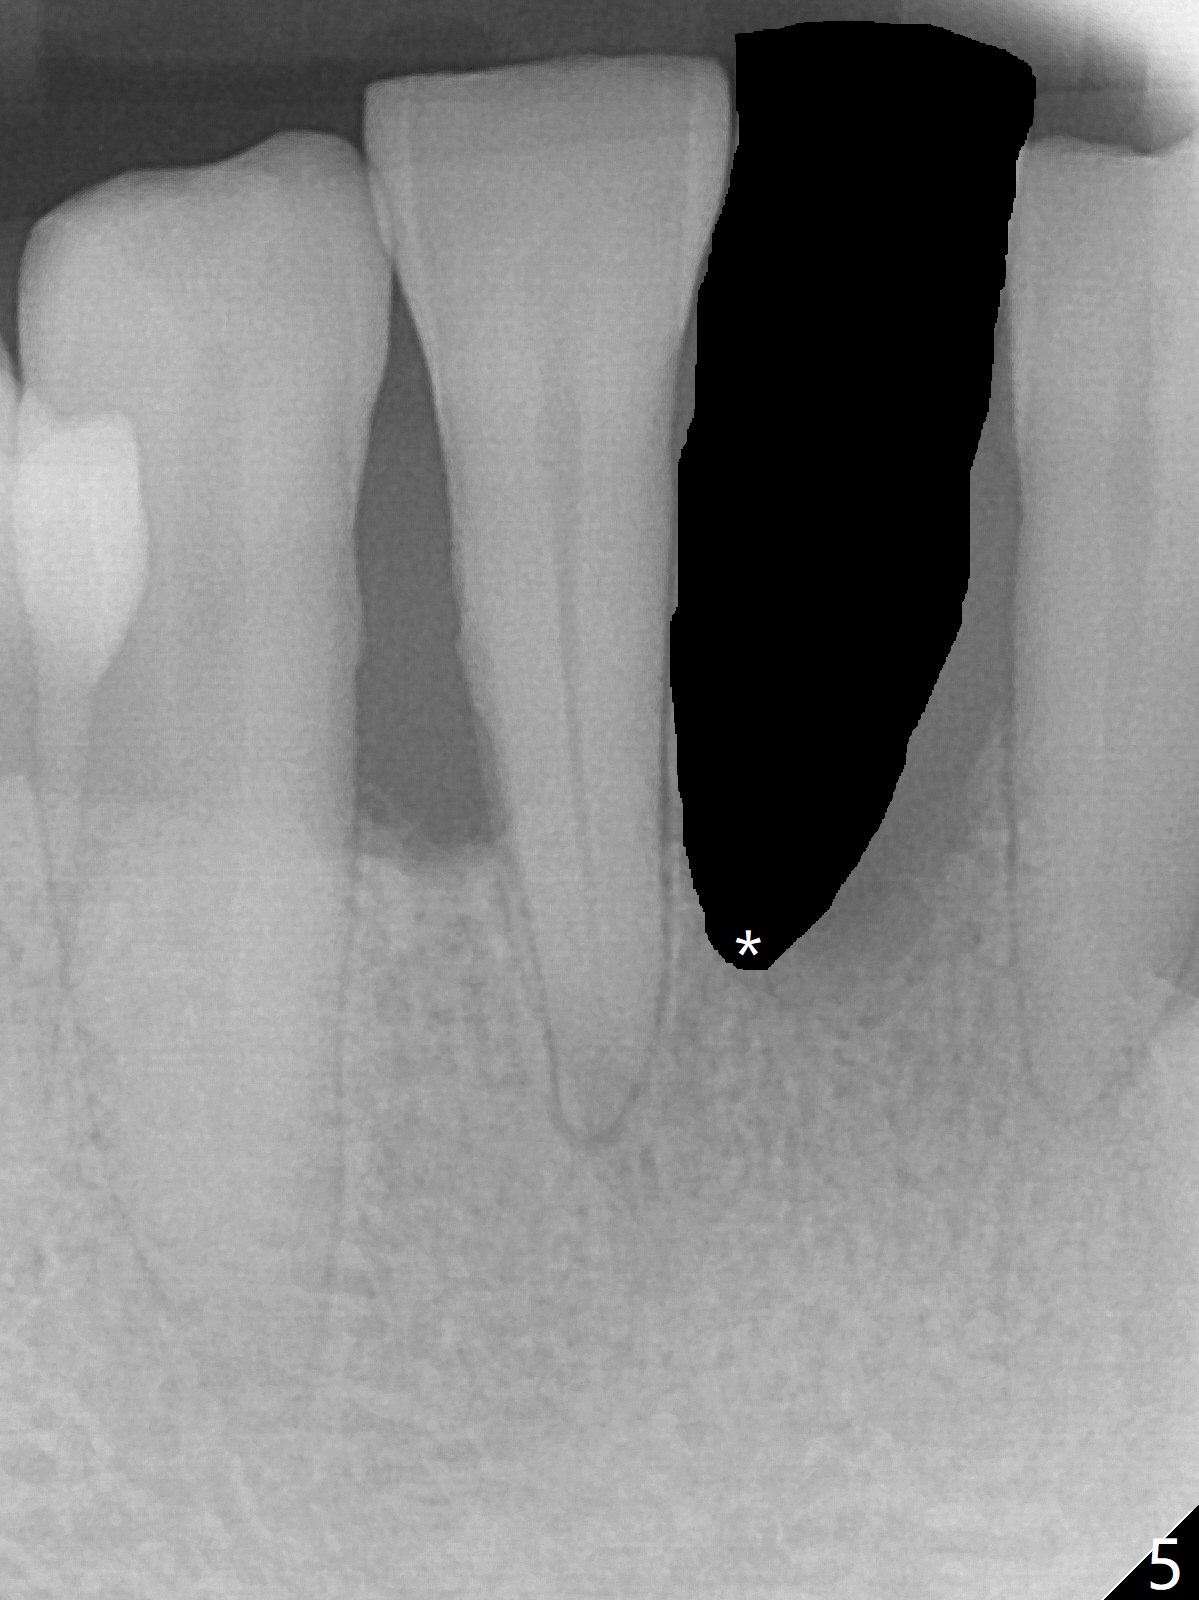

There is gingival inflammation at #25 buccally (Fig.1) and lingually (Fig.2). The bone loss is severe (Fig.3). Soft and hard tissue heights are 5 mm (cuff will be 4 mm) and 10 mm (implant will be 12 mm with 2 mm outside the native bone, Fig.4). The apex of the affected tooth appears deviated distal (Fig.5 *). The initial osteotomy happens to follow the long axis of the socket (Fig.6); to establish a correct trajectory, a new osteotomy should be made at the site labeled as a red line. In fact it is executed as planned (Fig.7). Because of the narrow flat ridge buccolingually, a 2.5x12(4) mm 1-piece implant is placed with >40 Ncm (Fig.8). With deeper placement of the implant, Vanilla graft is placed in 2 steps (Fig.9,10). The patient will return 2.5 months for extraction and implant of the fused teeth #22 and 23. No implant threads are exposed 10 months postop (Fig.11). CT taken 11 months postop shows that the 2.5 mm implant is in the middle of the bone (Fig.12) or 2 years post cementation (Fig.13).